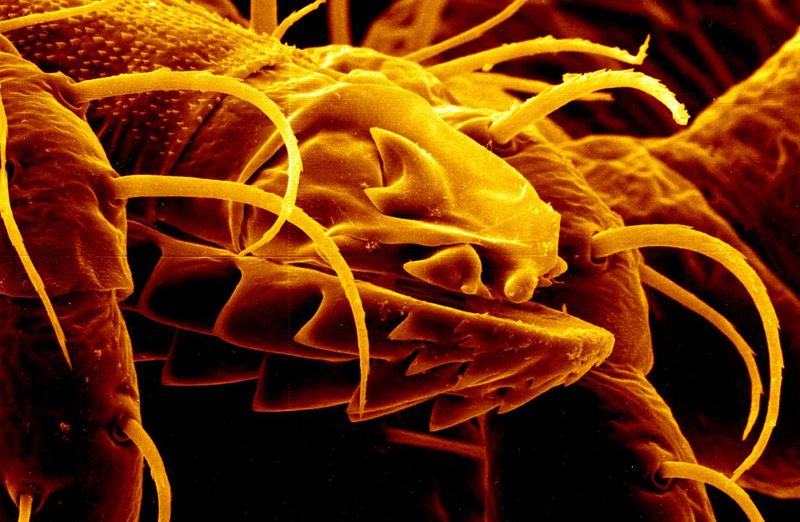

Beyond just making the imaging process easier, the images themselves are astonishingly clear and detailed. Have a look at some of these examples, provided by GE Healthcare:

The technology also makes it easier to view internal fixation devices, such as screws and plates.